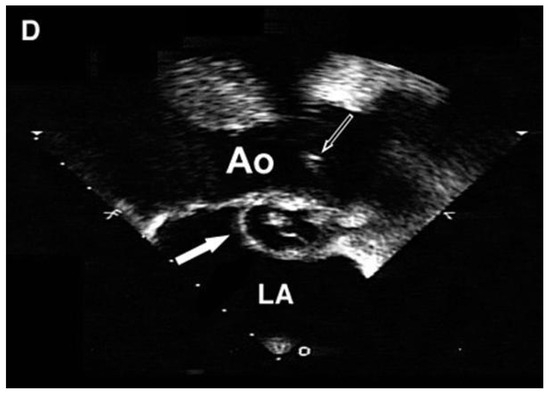

Carotid Restenosis: Incidence, Pathophysiology and Therapeutic Options

Restenosis after carotid endarterectomy and carotid artery stenting remains the main complication after both surgical and endovascular treatment of carotid stenosis, with a 2-year restenosis rate of 6–12%. Complex inflammation processes are the cause of early (<2 years) and late (>2 years) restenosis [...] Read more.

Restenosis after carotid endarterectomy and carotid artery stenting remains the main complication after both surgical and endovascular treatment of carotid stenosis, with a 2-year restenosis rate of 6–12%. Complex inflammation processes are the cause of early (<2 years) and late (>2 years) restenosis and principal systemic risk factors are female gender, hypertension, diabetes, dyslipidemia, and smoking. Non-procedural treatment includes lifestyle modifications and best medical therapy. The procedural treatment, considered mostly for symptomatic patients, includes different open and endovascular techniques. The management should be personalized according to patient and plaque characteristics. Full article

Show Figures

Graphical abstract